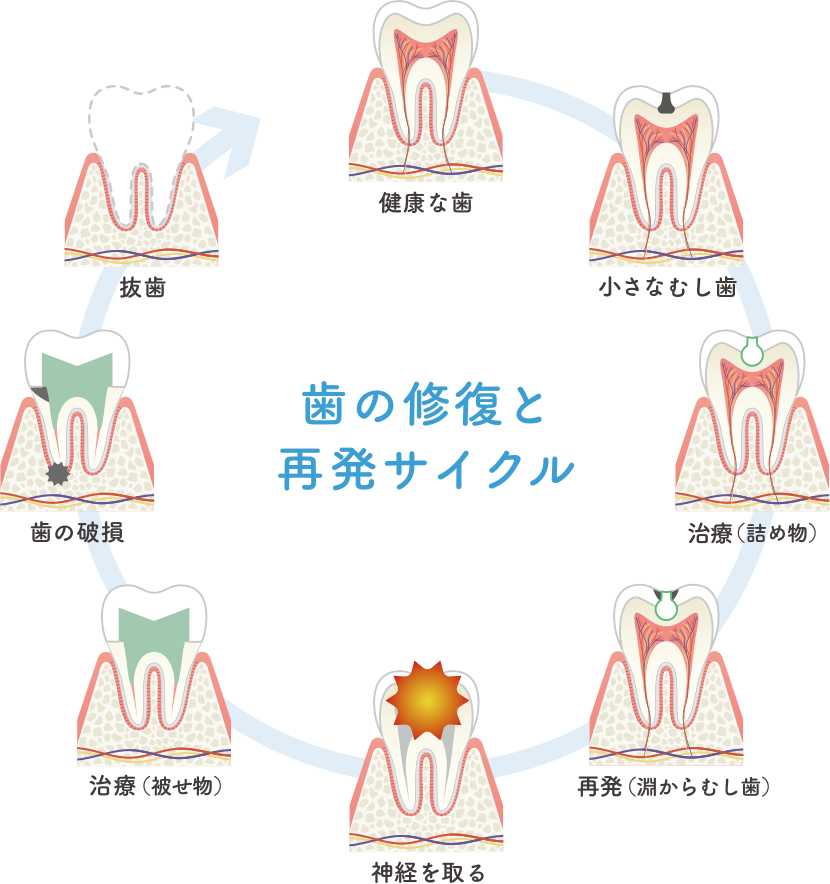

歯の修復と再発のサイクルを

考えた治療と経過観察

むし歯は治療した後に再発するリスクの高い病気です。一度治療した後、補修した部分と歯との隙間から再発を起こすことが多く、再発と修復を繰り返し、最終的に抜歯のリスクがあります。

むし歯は治療後の口腔管理により、再発を防ぐ処置を行うことが重要です。